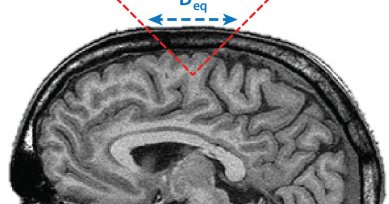

New in Brain Stimulation: "ITRUSST Consensus on Biophysical Safety for Transcranial Ultrasound Stimulation" by Jean-François Aubry et al. Establishing key guidelines for safe TUS application. Read the full text: https://t.co/aGbkkIH34d #Neuromodulation #TUS #BrainStim

Transcranial ultrasound stimulation (TUS) is an emerging technology for non-invasive brain stimulation. The International Transcranial Ultrasonic Stimulation Safety and Standards consortium (ITRUSST)...